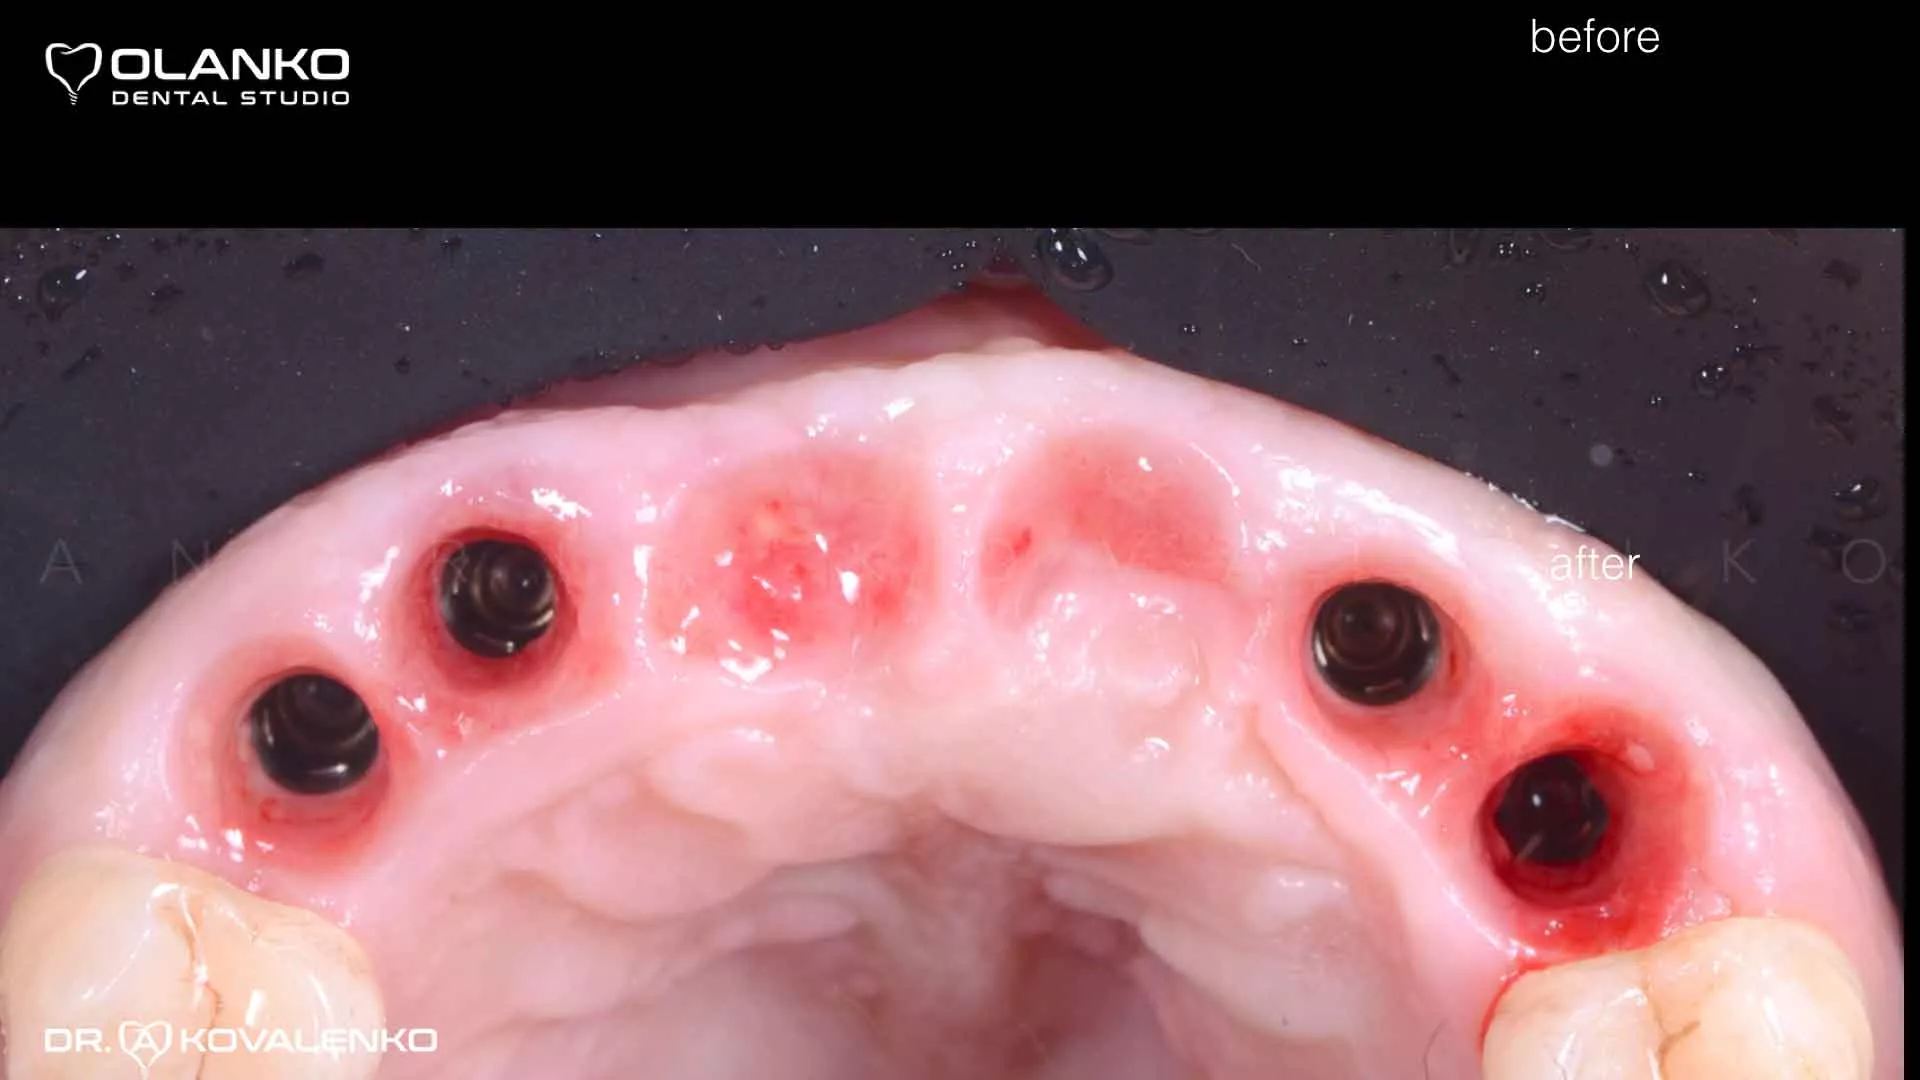

Фото вид десны вокруг имплантатов после приживления

Клинический случай 8 имплантация зубов

до

после